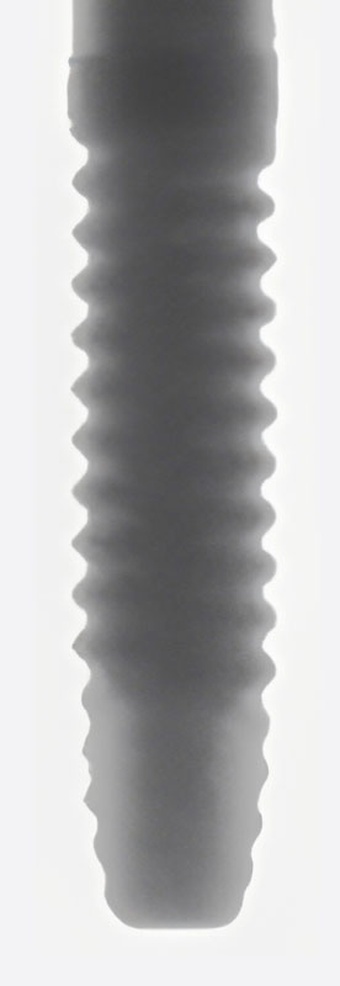

- Forma del cuerpo: Ápice cónico

- rosca del cuerpo: Diente de sierra inverso

- Forma del Ápice: Domo

- Agujero del Ápice: Sin agujero

- Ranuras del Ápice: Sí

Tapered Internal Tissue Level es un implante dental estándar producido por BioHorizons. Es un implante nivel de tejido. Su conexión es interna, de forma hexágono con bisel interno. Su cuerpo es ápice cónico con roscas diente de sierra inverso. Su cuello es ensanchado. Su cabeza tiene un bisel. Su ápice es domo, no tiene un agujero, y tiene ranuras. Está disponible en 4 diferentes diámetros y 4 diferentes longitudes. Este modelo de implante es bastante reciente. Requiere un destornillador de forma hexágono. Para más detalles, consulte el catálogo. BioHorizons también ofrece 23 otros modelos de implantes.